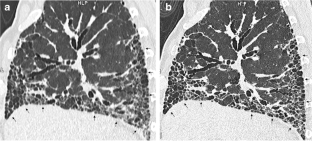

Fig. 1